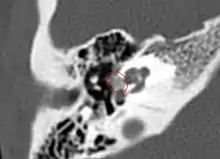

Otosclerosis on CT can be graded using the grading system suggested by Symons and Fanning.[21]

- Grade 1, solely fenestral;

- Grade 2, patchy localized cochlear disease (with or without fenestral involvement) to either the basal cochlear turn (grade 2A), or the middle/apical turns (grade 2B), or both the basal turn and the middle/apical turns (grade 2C); and

- Grade 3, diffuse confluent cochlear involvement (with or without fenestral involvement).

CT scan of otosclerotic focus in the anterior footplate

CT scan of otosclerotic focus in the anterior footplate